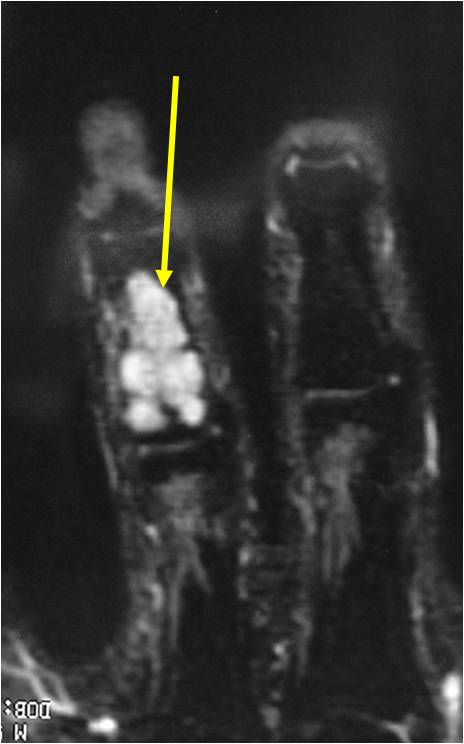

- MRI

- Lobulated margin

- Marked increased intensity long TR images

- Calcified chondroid – low intensity all sequences

MRI:

- Lobulated margin (Lobular Growth Pattern)

- T1 Weighted Images: Intermediate Signal Intensity

- Calcifications will be low signal

- T2 Weighted Images: High Signal Intensity

- High water content shows as high signal on T2 weighted images

Geographic lesion Stippled calcifications in lesion Phalanx is expanded Significant endosteal scalloping No cortical destruction No soft tissue extension Cortex Scalloped and Expanded